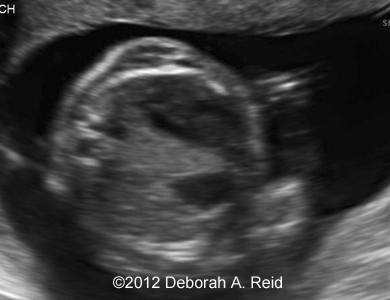

Ultrasound showed left-sided congenital diaphragmatic hernia with mild polyhydramnios.

The left-sided congenital diaphragmatic hernia contained a large portion of the bowel, spleen, stomach and the tip of the left lobe of the liver. In addition to the congenital diaphragmatic hernia, a sub-diaphragmatic sequestration was also noted which was confirmed by MRI.

Figure 1-10: The left-sided congenital diaphragmatic hernia contained a large portion of the bowel, spleen, stomach and the tip of the left lobe of the liver